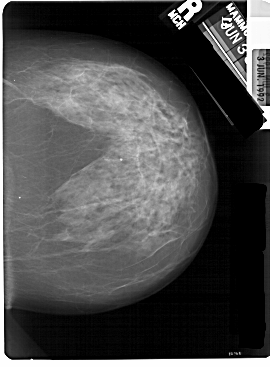

A_1824_1.RIGHT_MLO

RIGHT_CC LINES 5491 PIXELS_PER_LINE 4036 BITS_PER_PIXEL 12 RESOLUTION 43.5 NON_OVERLAY